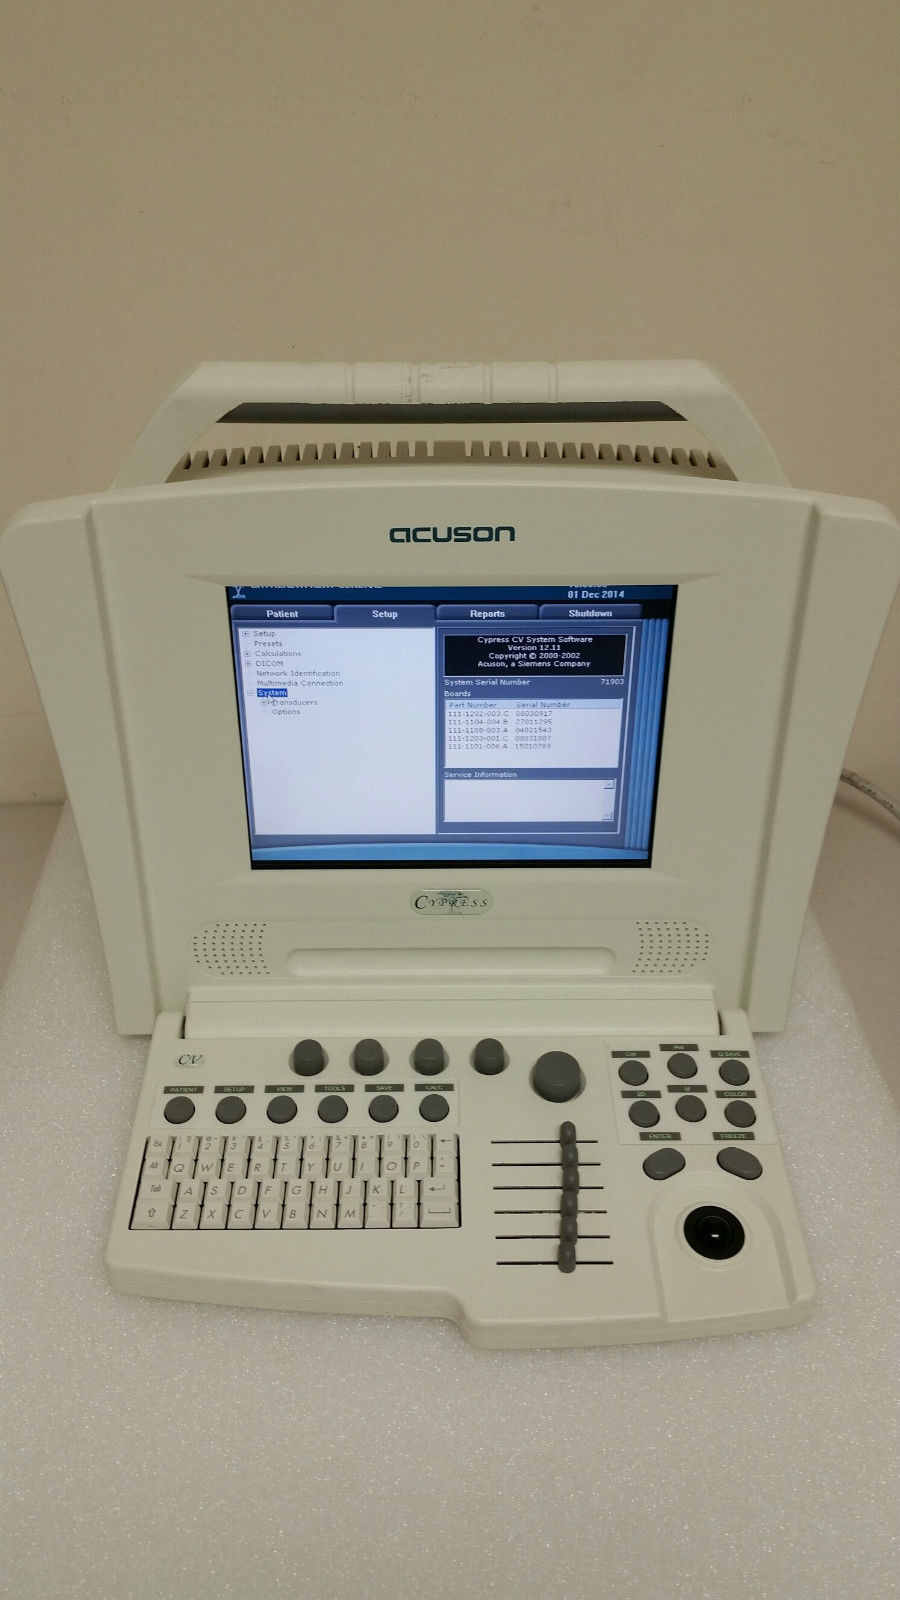

Explore the Acuson Cypress Cardiac Vascular Ultrasound Machine

Model: Cypress

The Acuson Cypress Cardiac Vascular Ultrasound Machine is engineered for exceptional imaging and diagnostic accuracy. Its advanced technology allows for detailed visualization of cardiac and vascular structures, which is essential for healthcare providers. The inclusion of the 3V2c and 7L3 probes enhances its versatility, making it suitable for various clinical applications. As a result, this machine is a crucial tool in modern cardiology and vascular assessment.

With a user-friendly interface, the Acuson Cypress simplifies the entire operation process. Health professionals can navigate through its features effortlessly, thanks to the intuitive design and layout. This ease of use not only speeds up the workflow but also improves the overall user satisfaction. Therefore, healthcare practitioners spend less time on technicalities and more on patient care and diagnostics.